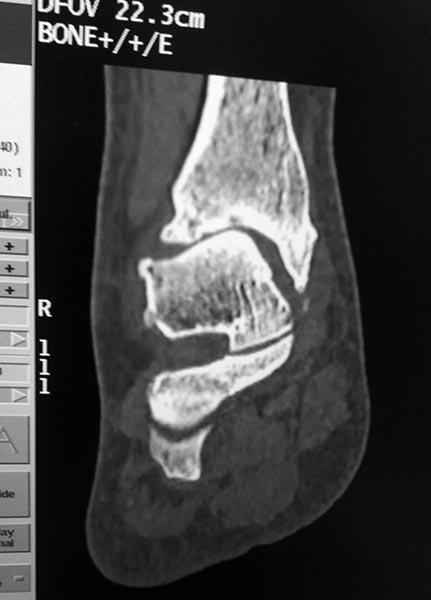

Добрый день!Обратилась женщина 1975 г.р. Жалобы на боль в голеностопном суставе при нагрузке (после ходьбы на расстояние 200 метров).

Травма три года назад. Упала с высоты своего роста, подвернула ногу, лечилась амбулаторно с Ds : растяжение связок голеностопного сустава. Rg не делали. После травмы боль осталась, в динамике интенсивность боли прогрессировала. Ухудшение в течении последних 6 мес. Местно : движения в голеностопном суставе в полном обьеме, отек незначительный. Пальпация безболезненна.Rg, Кт прилагается.Какова на ваш взгляд тактика лечения в данном случае?

Я бы еще повниматьнее к таранной кости присмотрелся. Не было ли перелома ее шейки? На КТ срез подозрительный, но только один.

Я тоже согласен, на одном из КТ-снимков, подозрение на перелом шейки таранной кости.

Также есть подозрение на перелом таранной кости по КТ.

Вколоченный перелом шейки таранной шейки кости,переднего края Б/берцовой кости.МОС шейки таранной кости,удаление костно-хрящевых экзостозов.